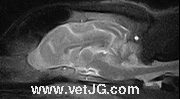

Siguiendo con nuestra

política de innovación y modernización, nuestro hospital ha incorporado

este novedoso método de diagnóstico que nos permite detectar y tratar

numerosas enfermedades neurológicas y no neurológicas que hasta ahora

eran infradiagnosticadas por los métodos tradicionales.

Es una técnica fiable, computerizada, de alta calidad, y segura, porque

entre otras cosas no emite radiaciones ionizantes tales como los rayos

X, por lo cual no se irradia al paciente ni al ambiente como se hace

por ejemplo con el TAC o con los aparatos de radiografías.